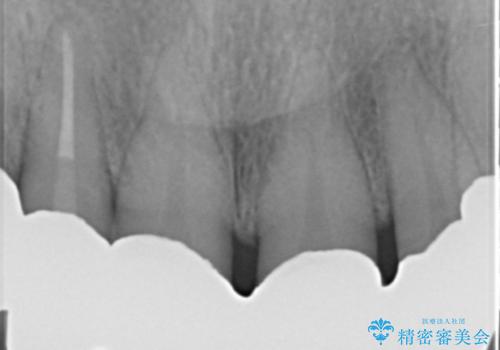

なるべく予算を抑えたいとのご希望から、上顎は入れ歯、右下臼歯部はインプラントによる治療を行いました。

インプラントの種類:スプラインツイスト